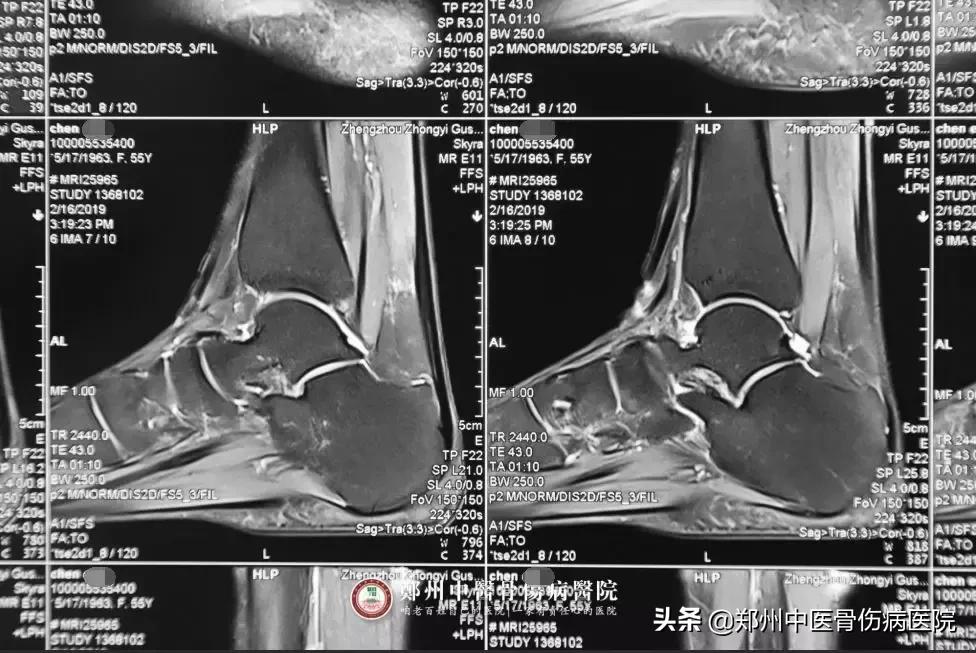

患者片子

陈女士的病情为什么久治不愈?陈志令主任经过影像学资料和体格检查,综合分析后发现症状原因,最终确诊为:1.左踝关节滑膜炎;2.左足骰骨错位症,随即制定了详细的治疗方案。